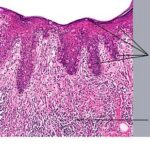

PATHOLOGY The intraepidermal adenocarcinoma of EMPD and MPD has a similar histologic appearance. There are groups, clusters, or single cells within the epidermis that show nuclear enlargement with atypia, prominent nucleoli, and well-defined ample cytoplasms . Intercellular bridges are absent. The cells can be within all levels of the epidermis and can compress but preserve the basal layer without junctional nest formation. The cells can extend into the contiguous epithelium of hair follicles and sweat gland ducts. Acanthosis, hyperkeratosis, and parakeratosis are often present. These cells have a “pagetoid” appearance and simulate other intraepidermal malignancies, including melanoma, pagetoid squamous cell carcinoma in situ, mycosis fungoides, cutaneous adnexal carcinomas (sebaceous carcinoma, porocarcinoma, and others), Merkel cell carcinoma, Langerhans cell histiocytosis, and other epidermotropic cutaneous metastases. The cells of MPD and EMPD can be pigmented, which should not necessarily indicate they are melanocytic. Paget's cells have intracellular mucopolysaccharides, with EMPD having a greater amount of mucin as compared